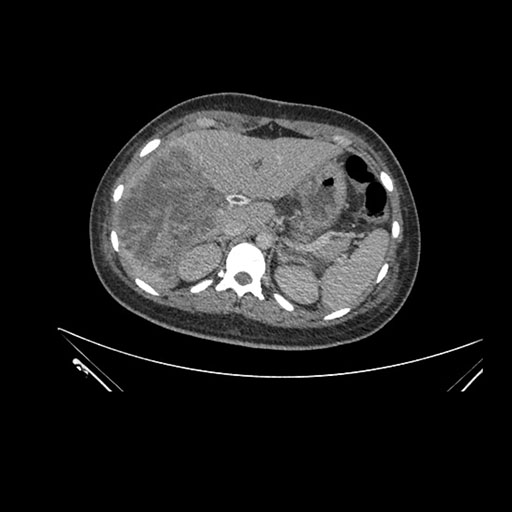

Imaging Analysis

Look through the patient's CT scan to identify any areas of concern for the necessary procedure.

Coronal Arterial

Based on initial findings, which issue(s) would you be most concerned about?